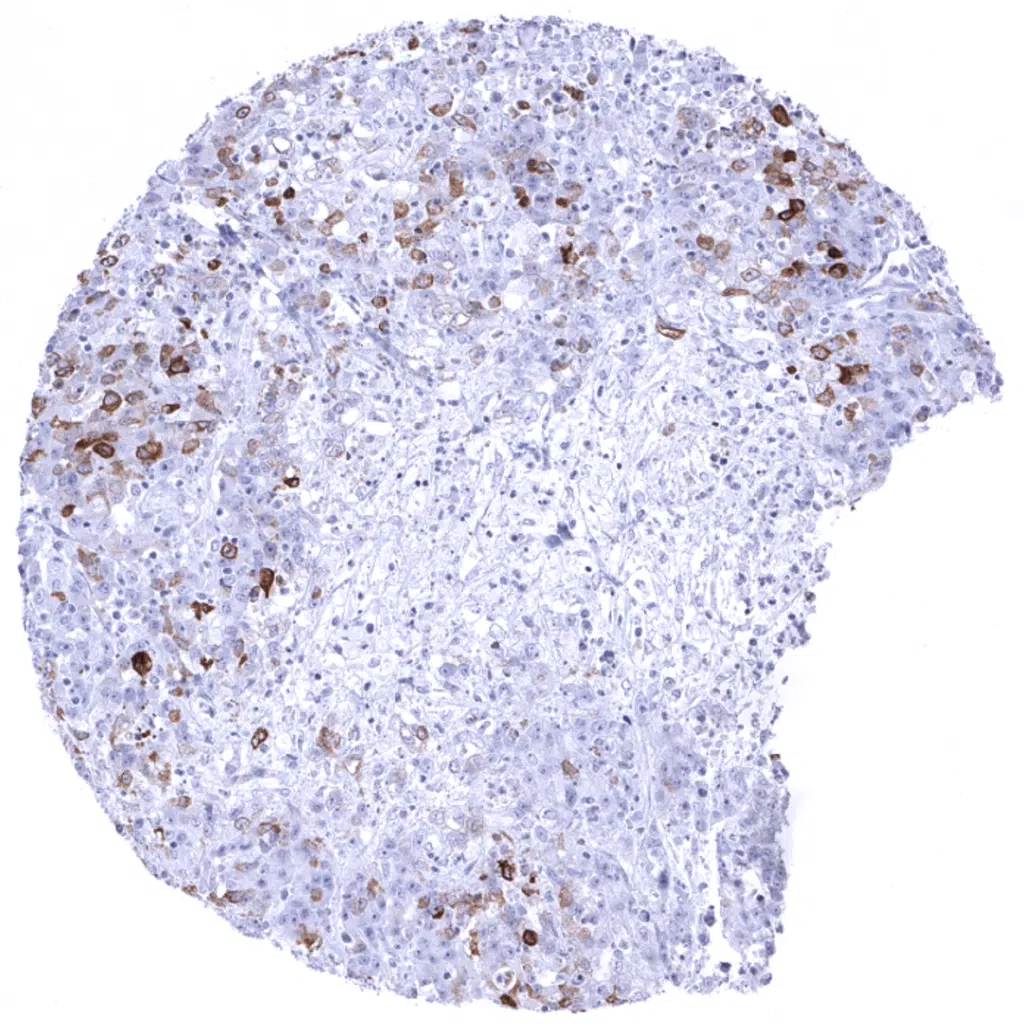

Colon- Colorectal adenocarcinoma containing areas with diffuse MUC5AC positivity next to areas with rather few interspersed MUC5AC positive cells.